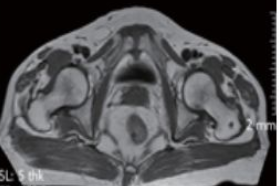

3.磁共振扫描(MRI)

影像学表现为:耻骨联合间隙可不同程度增宽,间隙内可见带状透亮间隙,单侧或双侧耻骨联合骨缘局限骨质硬化,少数囊变;耻骨联合骨缘锯齿状、鼠咬状、虫蚀状骨质破坏,边缘不光整,有时可见游离小骨块,早期骨质呈长T1长T2信号,晚期骨质均呈低信号。